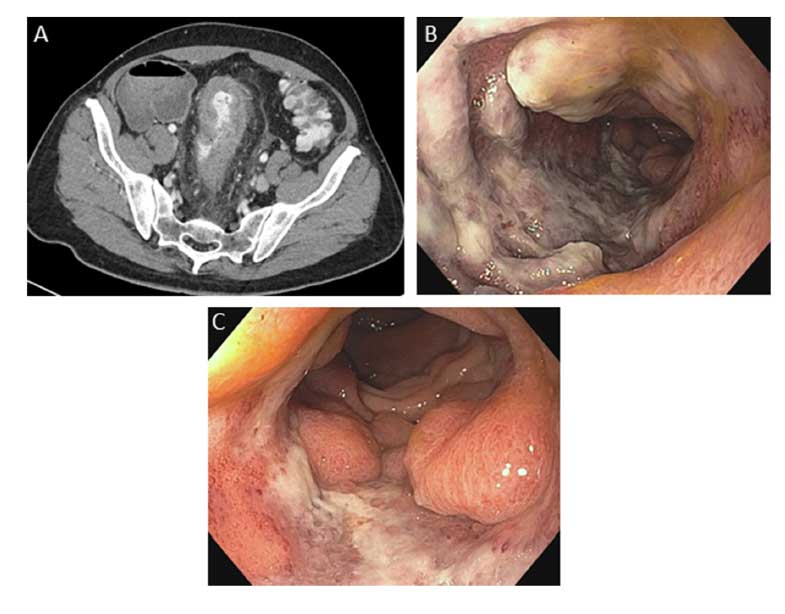

QUIZ: Um importante imitador